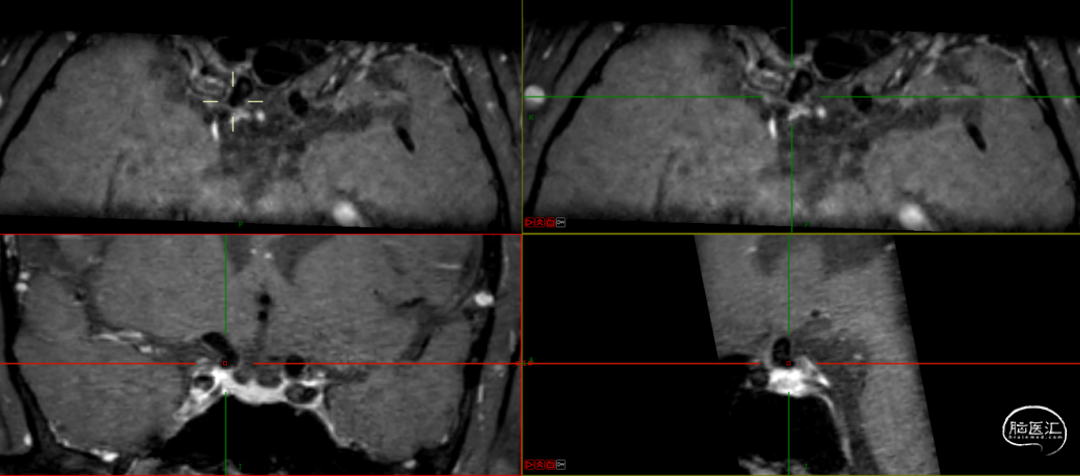

HRMR:

TEG: